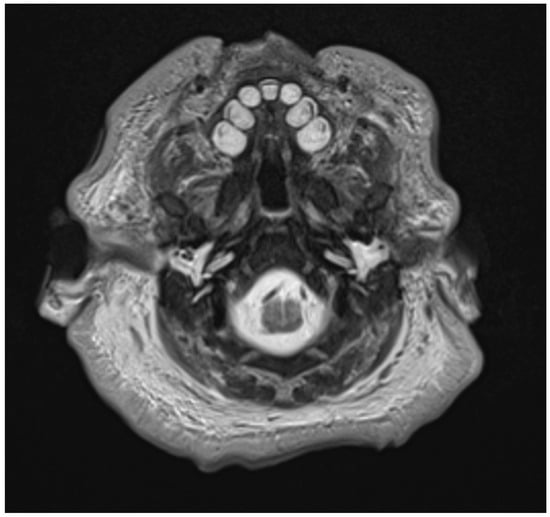

3.3. Radiologic Correlations of Embryological Development

- Hydrophilic tissues have greater water content and consequent higher signal on T2-weighted sequences and decreased density on CT;

- Calcification on MRI presents as hypointense on T2-weighted imaging. On CT, calcification presents as increased density with density greater or equal to bone.